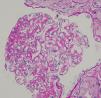

An 80-year-old Japanese man with stage G3a chronic kidney disease due to diabetes mellitus was admitted to the general medicine service for management of right haemopneumothorax after a motor vehicle accident and subsequent empyema caused by methicillin-sensitive Staphylococcus aureus treated with four weeks of intravenous cefazolin and drainage. The patient was seen in nephrology consultation for a rise in serum creatinine level from 1.4mg/dl upon admission to 5.3mg/dl (estimated glomerular filtration rate of 9ml/min/1.73m2) and purpuric lesions on the bilateral lower extremities. At the general medicine service, oral glucocorticoid was initiated for a presumed diagnosis of IgA vasculitis (Henoch-Schönlein purpura). However, the kidney function continued to worsen, and oliguria ensued despite infusion of lactated ringer's solution. Upon physical examination, he was not in distress. The blood pressure was 110/78mmHg. There were trace pretibial oedema and purpuric lesions on the bilateral legs. Urinalysis showed >100 red blood cells per high-power field (70% dysmorphic) and 5.2g/24h of proteinuria. Immunological analysis showed that increased immunoglobulins (IgG 1427mg/dl; IgA 1373mg/dl; IgM 48mg/dl) and decreased complement levels (C3 77mg/dl; C4 30mg/dl; CH50 44IU/ml). Antinuclear antibodies, antimyeloperoxidase antibodies, antiproteinase 3 antibodies, and a glomerular basement membrane antibody were negative. Renal biopsy showed 10 glomeruli, 4 of them sclerosed and 2 with endocapillary proliferation (Fig. 1). There was a mild interstitial infiltrate of polymorphonuclear cells, and the arteries had no significant lesions. Immunofluorescence microscopy showed diffuse depositions of IgA (Fig. 2) and C3. Electron microscopy could not be performed because of insufficient specimens. Based on clinical features and pathologic findings, IgA-IRGN was diagnosed. Intravenous cefazolin was administered for another four weeks, and oral glucocorticoid was tapered and stopped gradually without relapse of infection. However, the patient progressed to end-stage kidney disease even after 20mg of olmesartan was initiated.